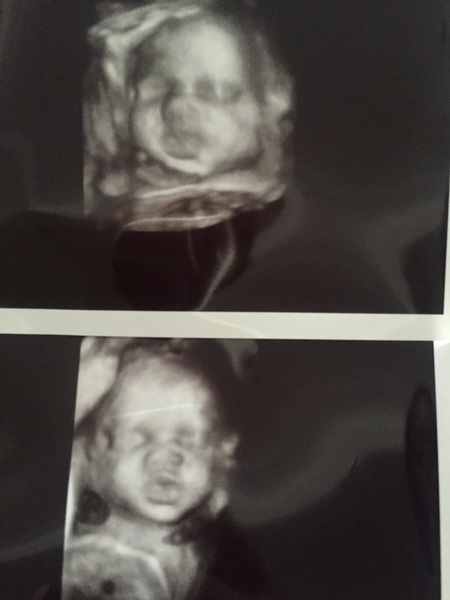

Really really can't wait to meet my lil man... So inlove already!

Ooo Dannie you have 3D, that's amazing. I bet it feels so good being able to see him like that Grin

danni oh my god that is adorable! Look at those little lips!!!!! ❤❤❤

Danni what an adorable boy, it's amazing the detail you can see on their little faces!

Thanks girls.. He's his dad's double.